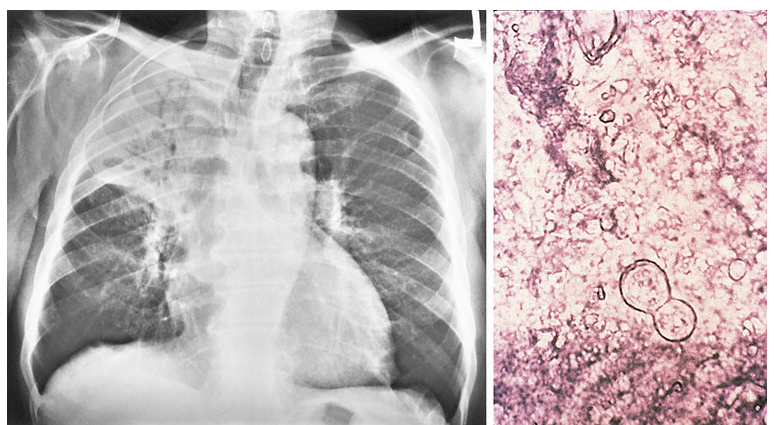

72yo with 4month hx leg swelling & increased abdominal girth. 2-year hx progressive sob. was a sandblaster.

silicosis

give o2